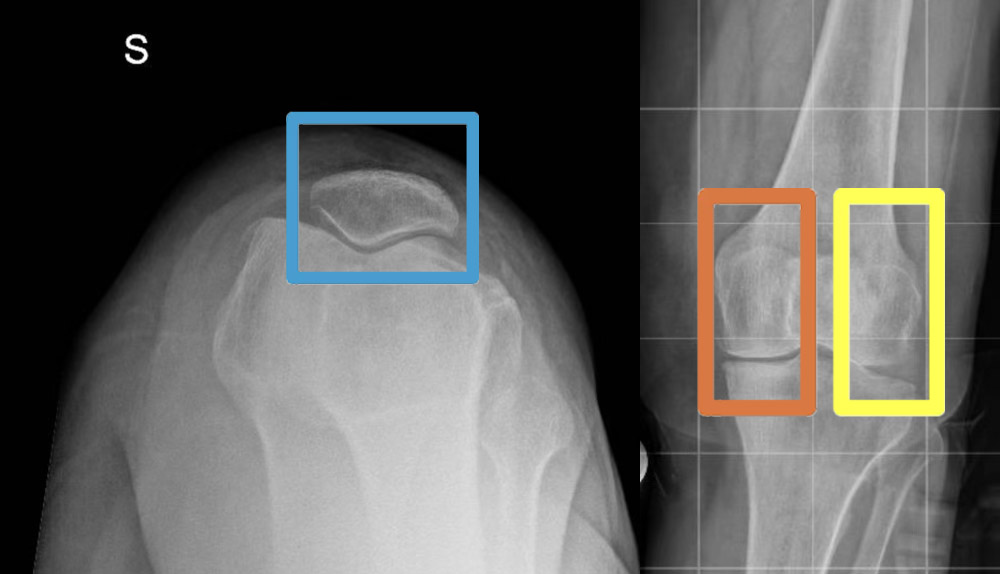

- RX assiale di rotula: Indispensabile per lo studio della congruenza e della posizione della rotula nell’articolazione femoro-rotulea.

- Radiografie in proiezione Rosenberg: Permettono di analizzare il comparto mediale e laterale in carico e in dinamica, identificando segni precoci di usura cartilaginea.